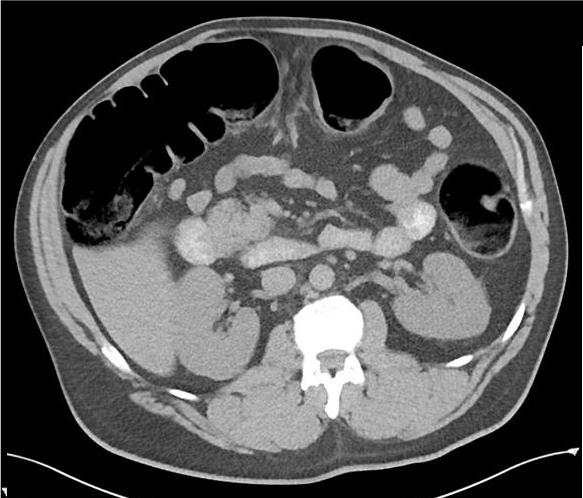

Image de l'occlusion du colon

haustral est intercale . Image TDM en coupe coronale |

Meme cas en coupe axilae .

normale ) |